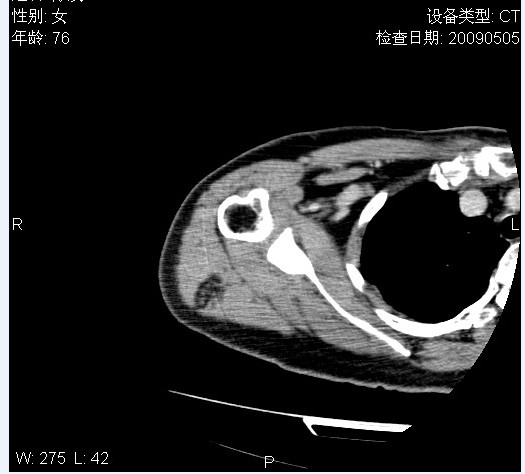

标题: CT19811:女,76岁,右上臂肿物1个月 [打印本页]

标题: CT19811:女,76岁,右上臂肿物1个月

使用了造影剂,可惜效果不太好

右肱骨上段软组织内见梭形低密度影,边界清楚,最长径约54mm.

病理结果:脂肪瘤。术中见肱骨骨膜受侵,有出血,量不详。

当时诊断意见:右肩三角肌内蔓状血管瘤(先天性动静脉瘘)。

本人对病理结果有个疑问:单纯的脂肪瘤内为什么有条状软组织影,那应该脂肪肉瘤才对啊?

该病例增强效果欠佳,由于经验欠缺,我们注射对比剂是由下肢足背静脉给药。注速2.0。虽然如此,但我们可以看到肿块内部条状软组织影是强化的,而且是连续的,并可见供血动脉是由腋动脉的其中一支即肩胛下动脉分出。从这些征象我们可以得出诊断:蔓状务血管瘤。

可病理偏偏为脂肪瘤,我怀疑取材有问题。因为蔓状血管瘤异常扩张的静脉外周是脂肪成分,它可以侵犯肌组织及骨骼。当取材于外周,那当然是脂肪瘤。此时我认为临床的最终诊断不应单从病理出发,应该综合考虑。